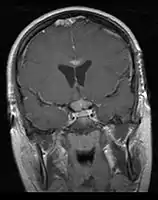

• Mainly located in midline structures, suprasellar region or pineal gland, also basal ganglia and hypothalamus

Location